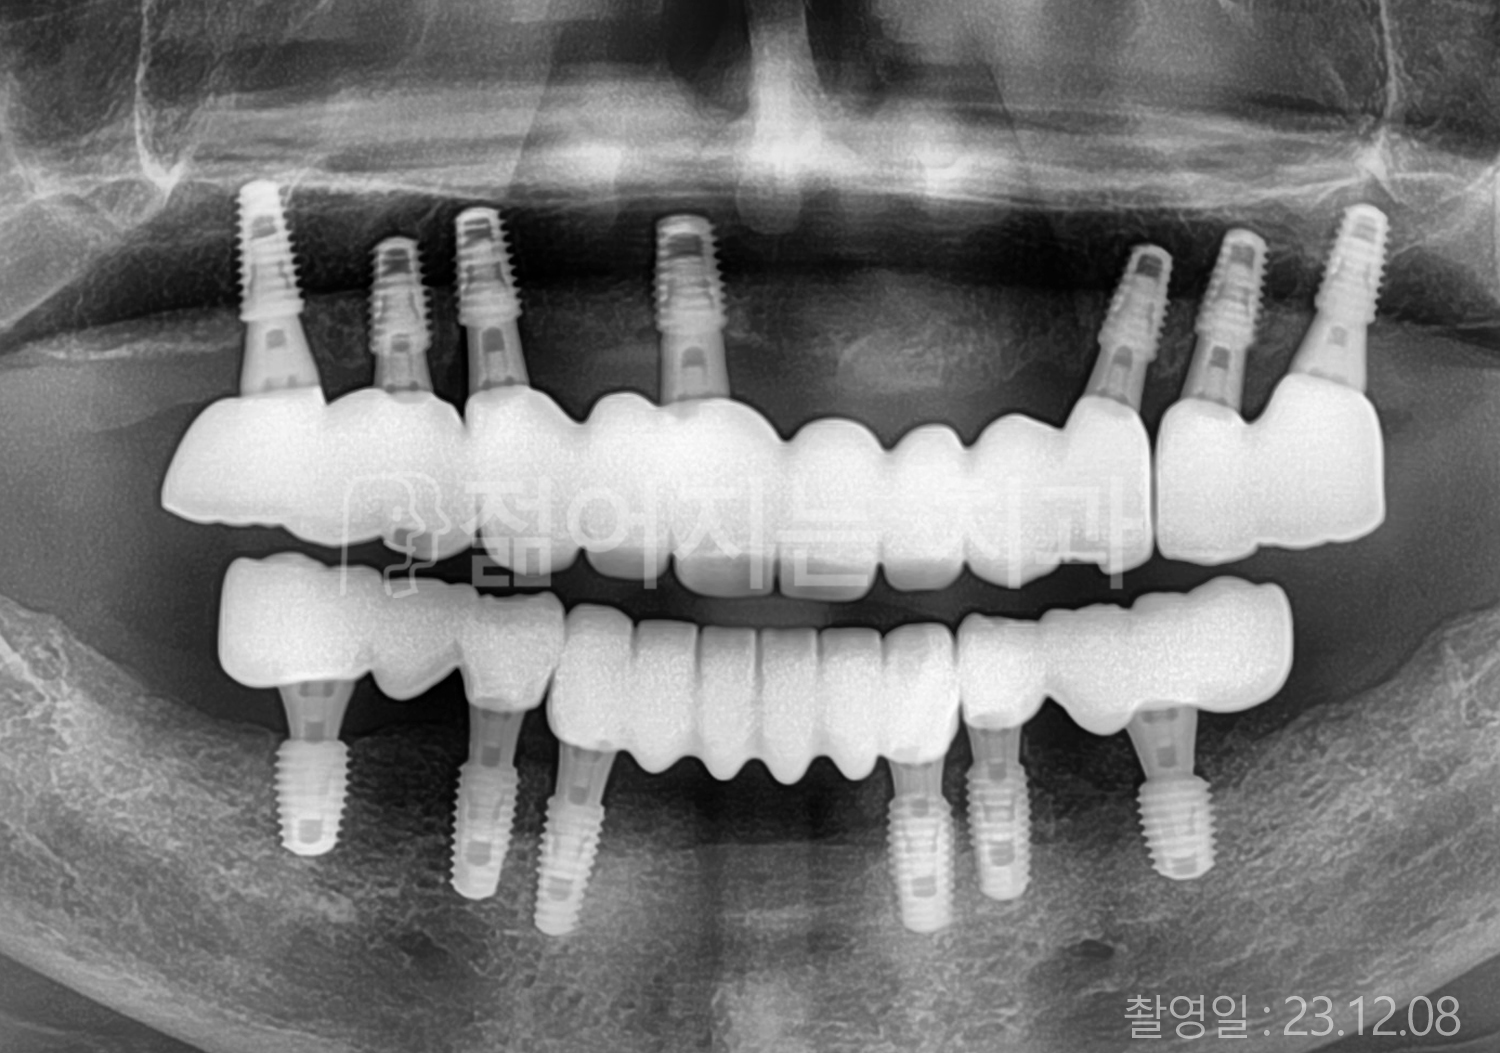

치료부위

식립개수

특이사항

• 70대 전체치아 10개 이상 임플란트